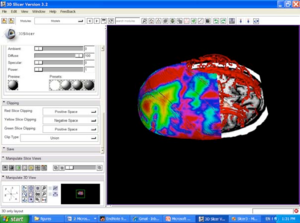

Publication: PLoS One. 2016 Jan 11;11(1):e0145987. PMID: 26751685 | PDF Authors: Zhan Q, Chen X. Institution: School of Mechanical Engineering, Shanghai Jiao Tong University, Shanghai, China. Background/Purpose: This paper proposes an interactive method of model clipping for computer-assisted surgical planning. The model is separated by a data filter that is defined by the implicit function of the clipping path. Being interactive to surgeons, the clipping path that is composed of the plane widgets can be manually repositioned along the desirable presurgical path, which means that surgeons can produce any accurate shape of the clipped model. The implicit function is acquired through a recursive algorithm based on the Boolean combinations (including Boolean union and Boolean intersection) of a series of plane widgets' implicit functions. The algorithm is evaluated as highly efficient because the best time performance of the algorithm is linear, which applies to most of the cases in the computer-assisted surgical planning. Based on the above stated algorithm, a user-friendly module named SmartModelClip is developed on the basis of Slicer platform and VTK. A number of arbitrary clipping paths have been tested. Experimental results of presurgical planning for three types of Le Fort fractures and for tumor removal demonstrate the high reliability and efficiency of our recursive algorithm and robustness of the module. Funding:

A snapshot of the module SmartModelClip in 3D Slicer. On the left is the operator command view that users can create and manipulate clipping path and thickness plane(i.e., they can create, hide and delete plane widgets). Users can also reverse the directions of the axes of the both clipping path and thickness plane widget. On the right is the scene that users can interact with the clipping path. They can specify the fiducial points that position the clipping path and modify the boundary of the clipping path by dragging the handles to obtain the desirable clipping path. |